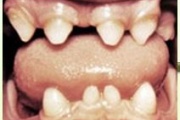

Lutipudelikaariese kahjustused

Lutipudelikaaries